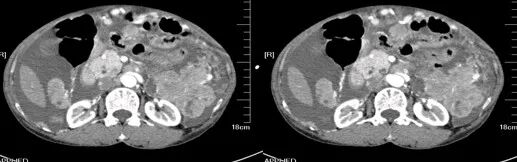

肾挫伤

肾挫伤是一种比较多见的肾损伤,肾组织损伤较轻,肾包膜和肾盂大多保持完整,肾实质内产生瘀血或血肿,并有少量血液流入肾盂导致血尿。肾挫伤在X线造影片上可不显示形态上的改变。一般均能自行愈合而不造成严重后果。